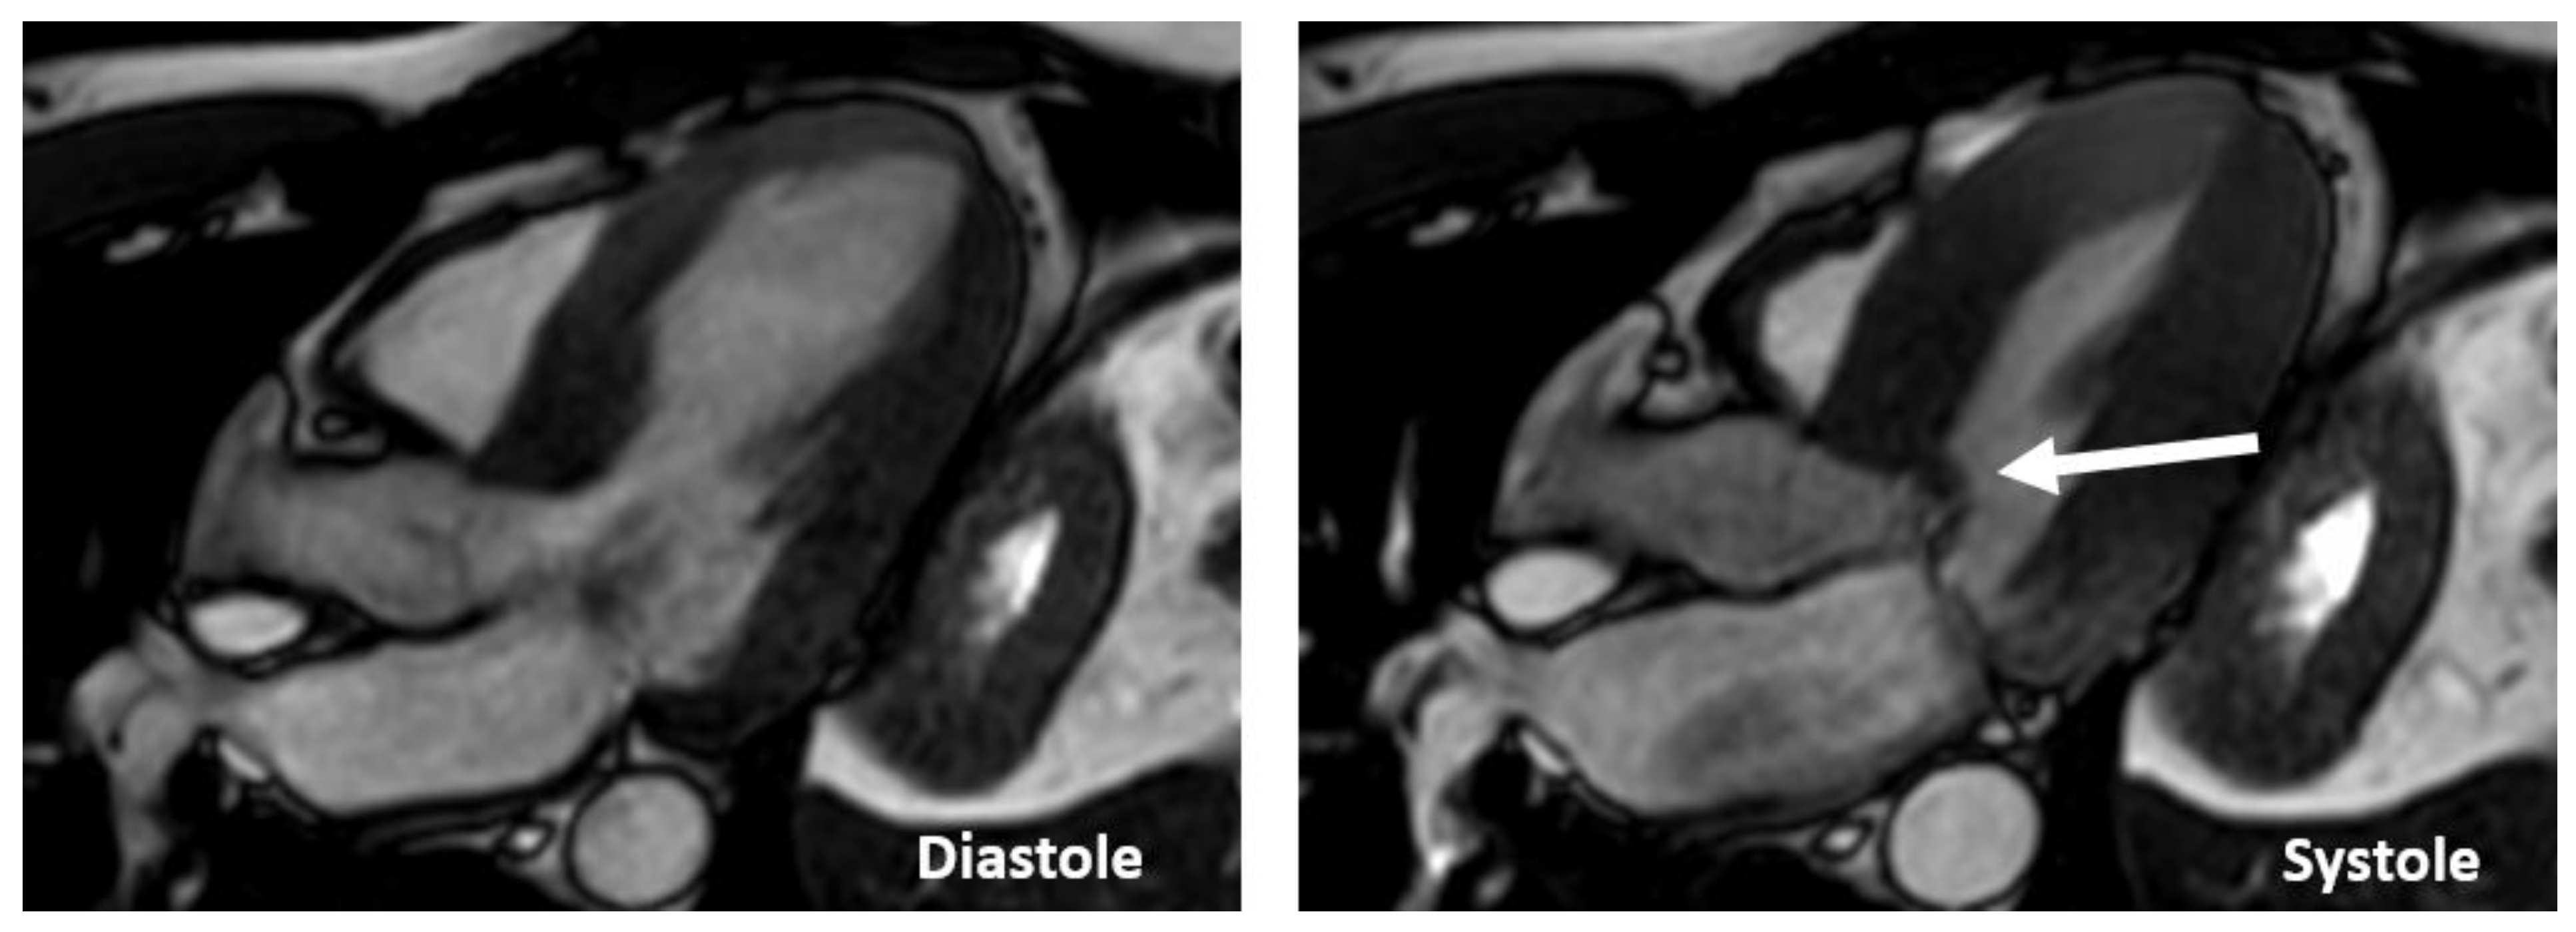

CMR is superior to standard 2D echocardiography in the detection of LV apical and anterolateral hypertrophy, apical aneurysms, thrombi, myocardial crypts, and papillary muscle abnormalities; however, small structures, such as the mitral valve apparatus, are not well-visualized because imaging slices in CMR are thick and potentially lead to partial volume artifacts (Figure 11).

Figure 11.

Images of long-axis CMR view of a patients with HCM showing SAM (arrow).